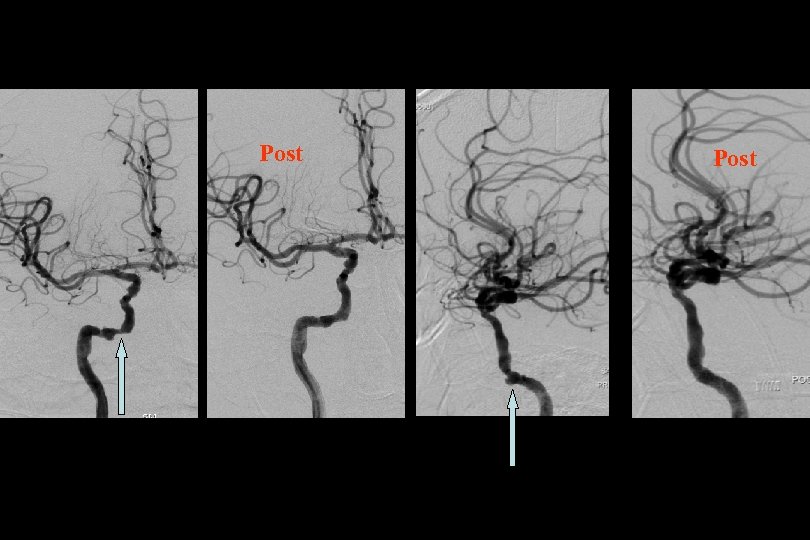

52 y kadın efektiv/test edilmiş ikili antiagregan ted altında iken multipl TIA Basit PTA sonrası

1. Yıl kontrol

1 yıl kontrol PTA Sonrası